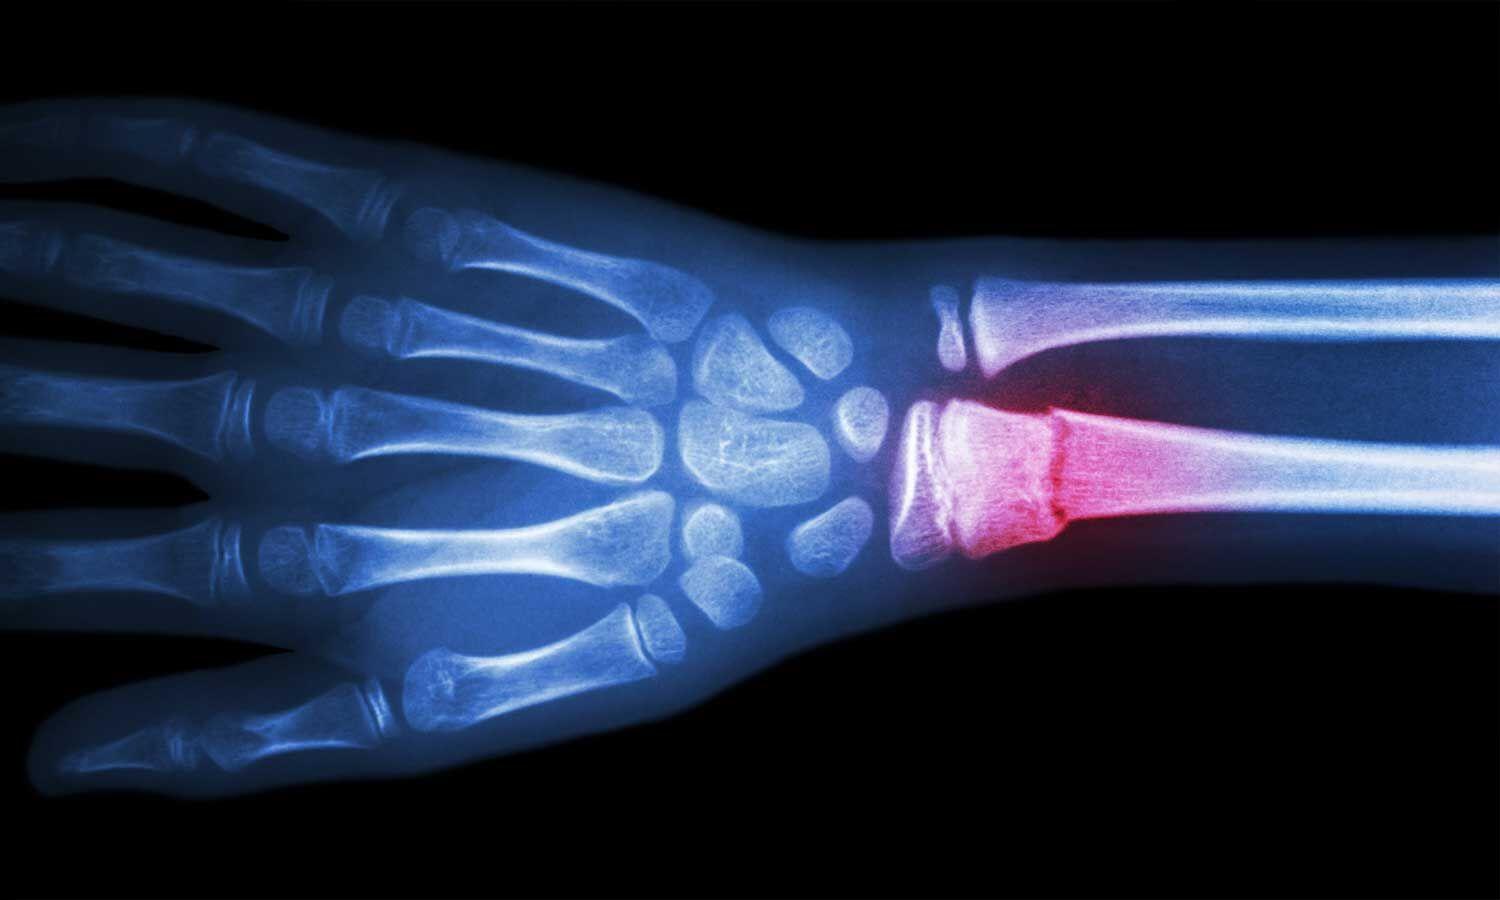

骨折部位好發於腕部橈骨,髖部股骨頸,肩部及脊椎骨椎體位置。停經或卵巢切除等婦人,因為雌激素合成量突然減少,體內破骨細胞活性增強,體內造骨細胞活性減弱,合成骨量減少。所以西醫常常建議要補充大豆異黃酮去補充荷爾蒙,而黃豆也富含蛋白質與雌激素,對於骨質疏鬆有幫助。

手腕多為骨質疏鬆患者首個骨折位置,常因跌倒時欲用手撐地造成。